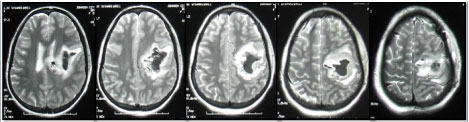

A T2-weighted MRI revealed a cavitating intracerebral hematoma in the distribution of the middle division of the left middle cerebral artery (Figure 1). A left carotid angiogram was notable for the presence of an AVM involving the distal portion of the medial division of the middle cerebral artery (Figure 2).

Figure 1: T2-weighted MRI showing a cavitating intracranial hematoma in the distribution of the middle branch of the left middle cerebral artery. The hematoma has ruptured into the lateral ventricle (first frame on left) causing blood to appear in the subarachnoid space. The hematoma has shifted the midline to the right (best seen in the second and third frames from the left).